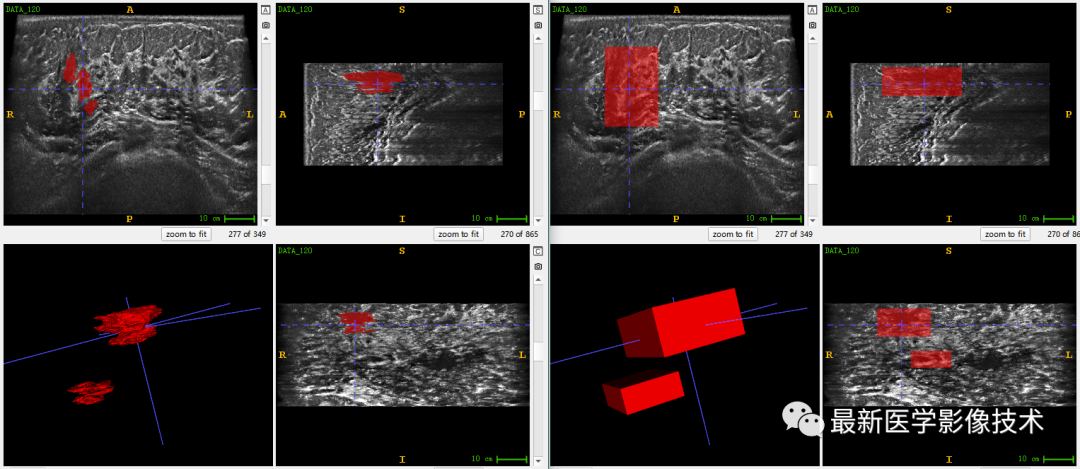

乳腺肿瘤分割采用两阶段分割网络,第一个网络进行粗分割定位肿瘤位置,第二个网络进行精分割得到肿瘤精确轮廓,然后在根据精分割mask和对应ROI图像进行良恶性分类。具体实现可以参考这篇文章TDSC-ABUS2023——2023 年自动化 3D 乳腺超声 (ABUS) 的肿瘤检测、分割和分类挑战.

验证集分割和检测部分结果如下所示。